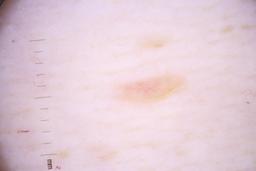

ISIC_4077341

Clinical

| Field | Value |

|---|---|

| acquisition_day | 1 |

| age_approx | 50 |

| anatom_site_1 | Trunk |

| anatom_site_2 | Anterior trunk |

| concomitant_biopsy | False |

| dermoscopic_type | contact non-polarized |

| diagnosis_1 | Benign |

| diagnosis_confirm_type | serial imaging showing no change |

| family_hx_mm | False |

| image_type | dermoscopic |

| lesion_id | IL_9238622 |

| patient_id | IP_1969685 |

| personal_hx_mm | True |

| sex | male |

Columns

Showing first 50 images.